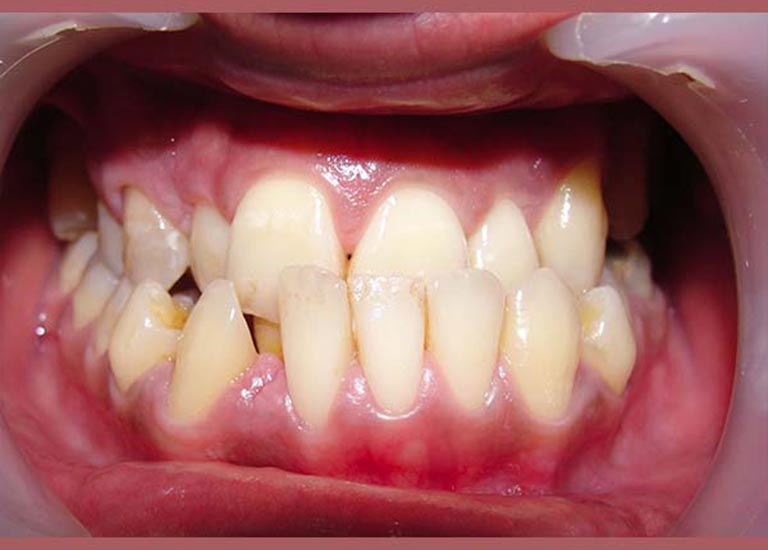

AFTER

After examining the case, I have conveyed the good news to our friend, that despite the difficulty of his case, we were able to reach a satisfying result through orthodontic treatment. As expected, tooth extraction was nessecary, to open space for the rest of his teeth to arrange and treat the anterior crossbite. At the end of the treatment, most of our friend’s dental problems were treated, and he could smile happily and with confidence.